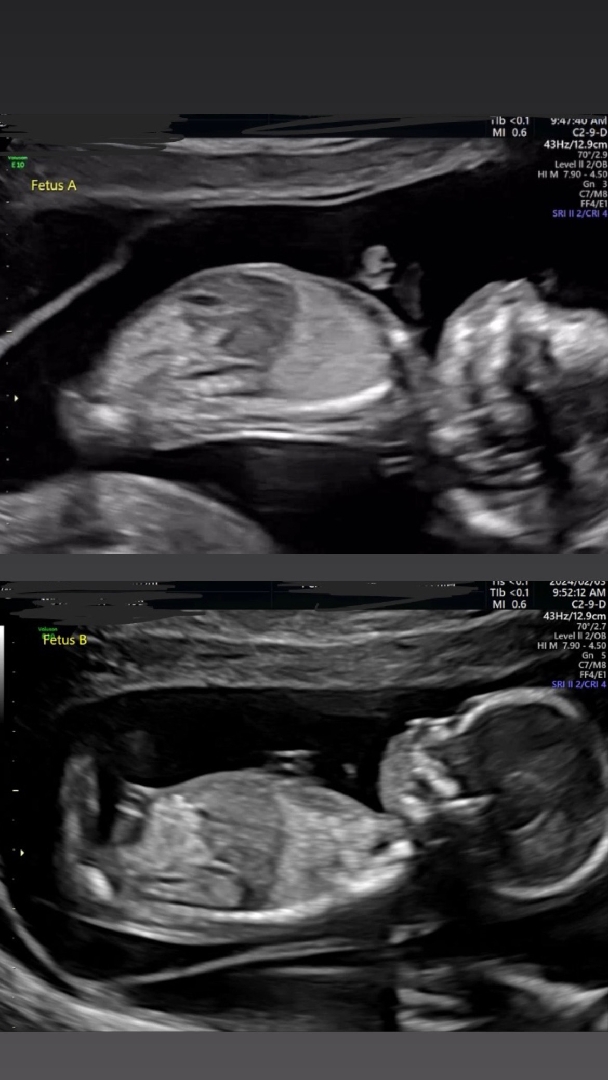

14주 5일된 쌍둥이 초음파 사진입니다. 제 생각엔 첫번째는 딸, 두번째는 아들 같은데 여러분들의 많은 의견 기다립니다^^